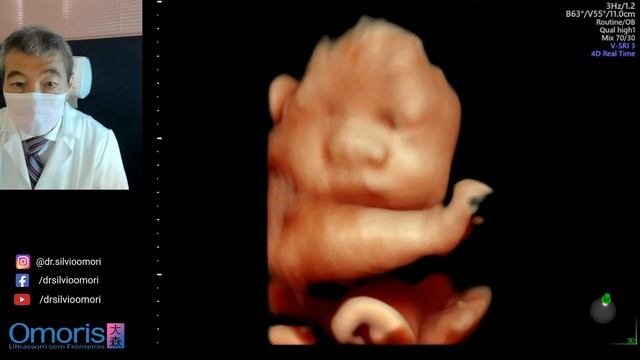

ULTRASSOM 3D 4D. Gravidez 31 semanas. Imagens volumétricas.